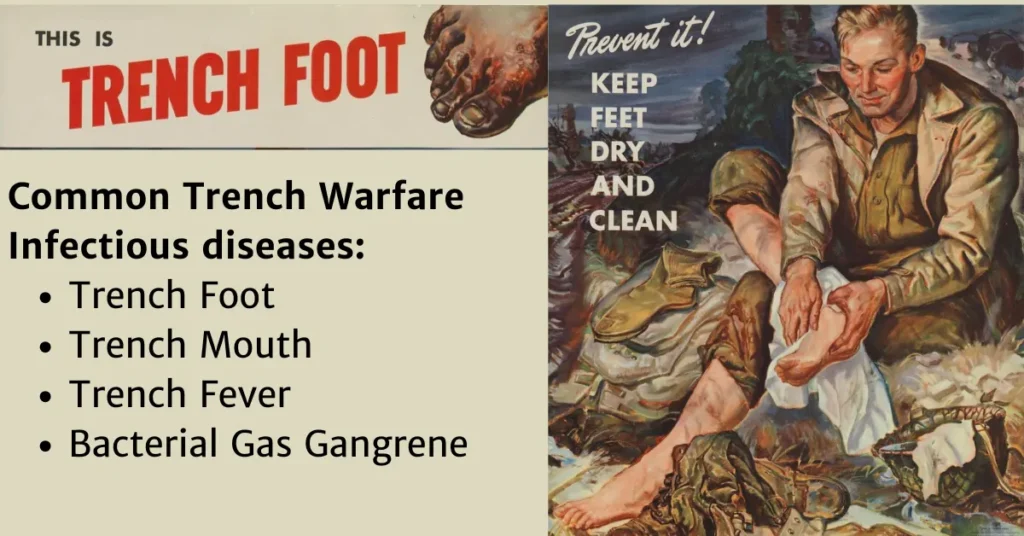

Trench foot, or more accurately immersion foot, is a byproduct of continued damp exposure of the feet in non-freezing, but cold conditions, resulting in initially non-infectious skin damage that frequently becomes infected and in severe cases, progresses to gangrene with resultant need for amputation.

It was a significant enough problem during WW1 that the US military created posters during WW2 to educate soldiers about how to prevent it. Ironically today, it occurs at outdoor music festivals. At the 1998 Glastonbury music festival, doctors were seeing approximately ninety people a day with Immersion Foot.